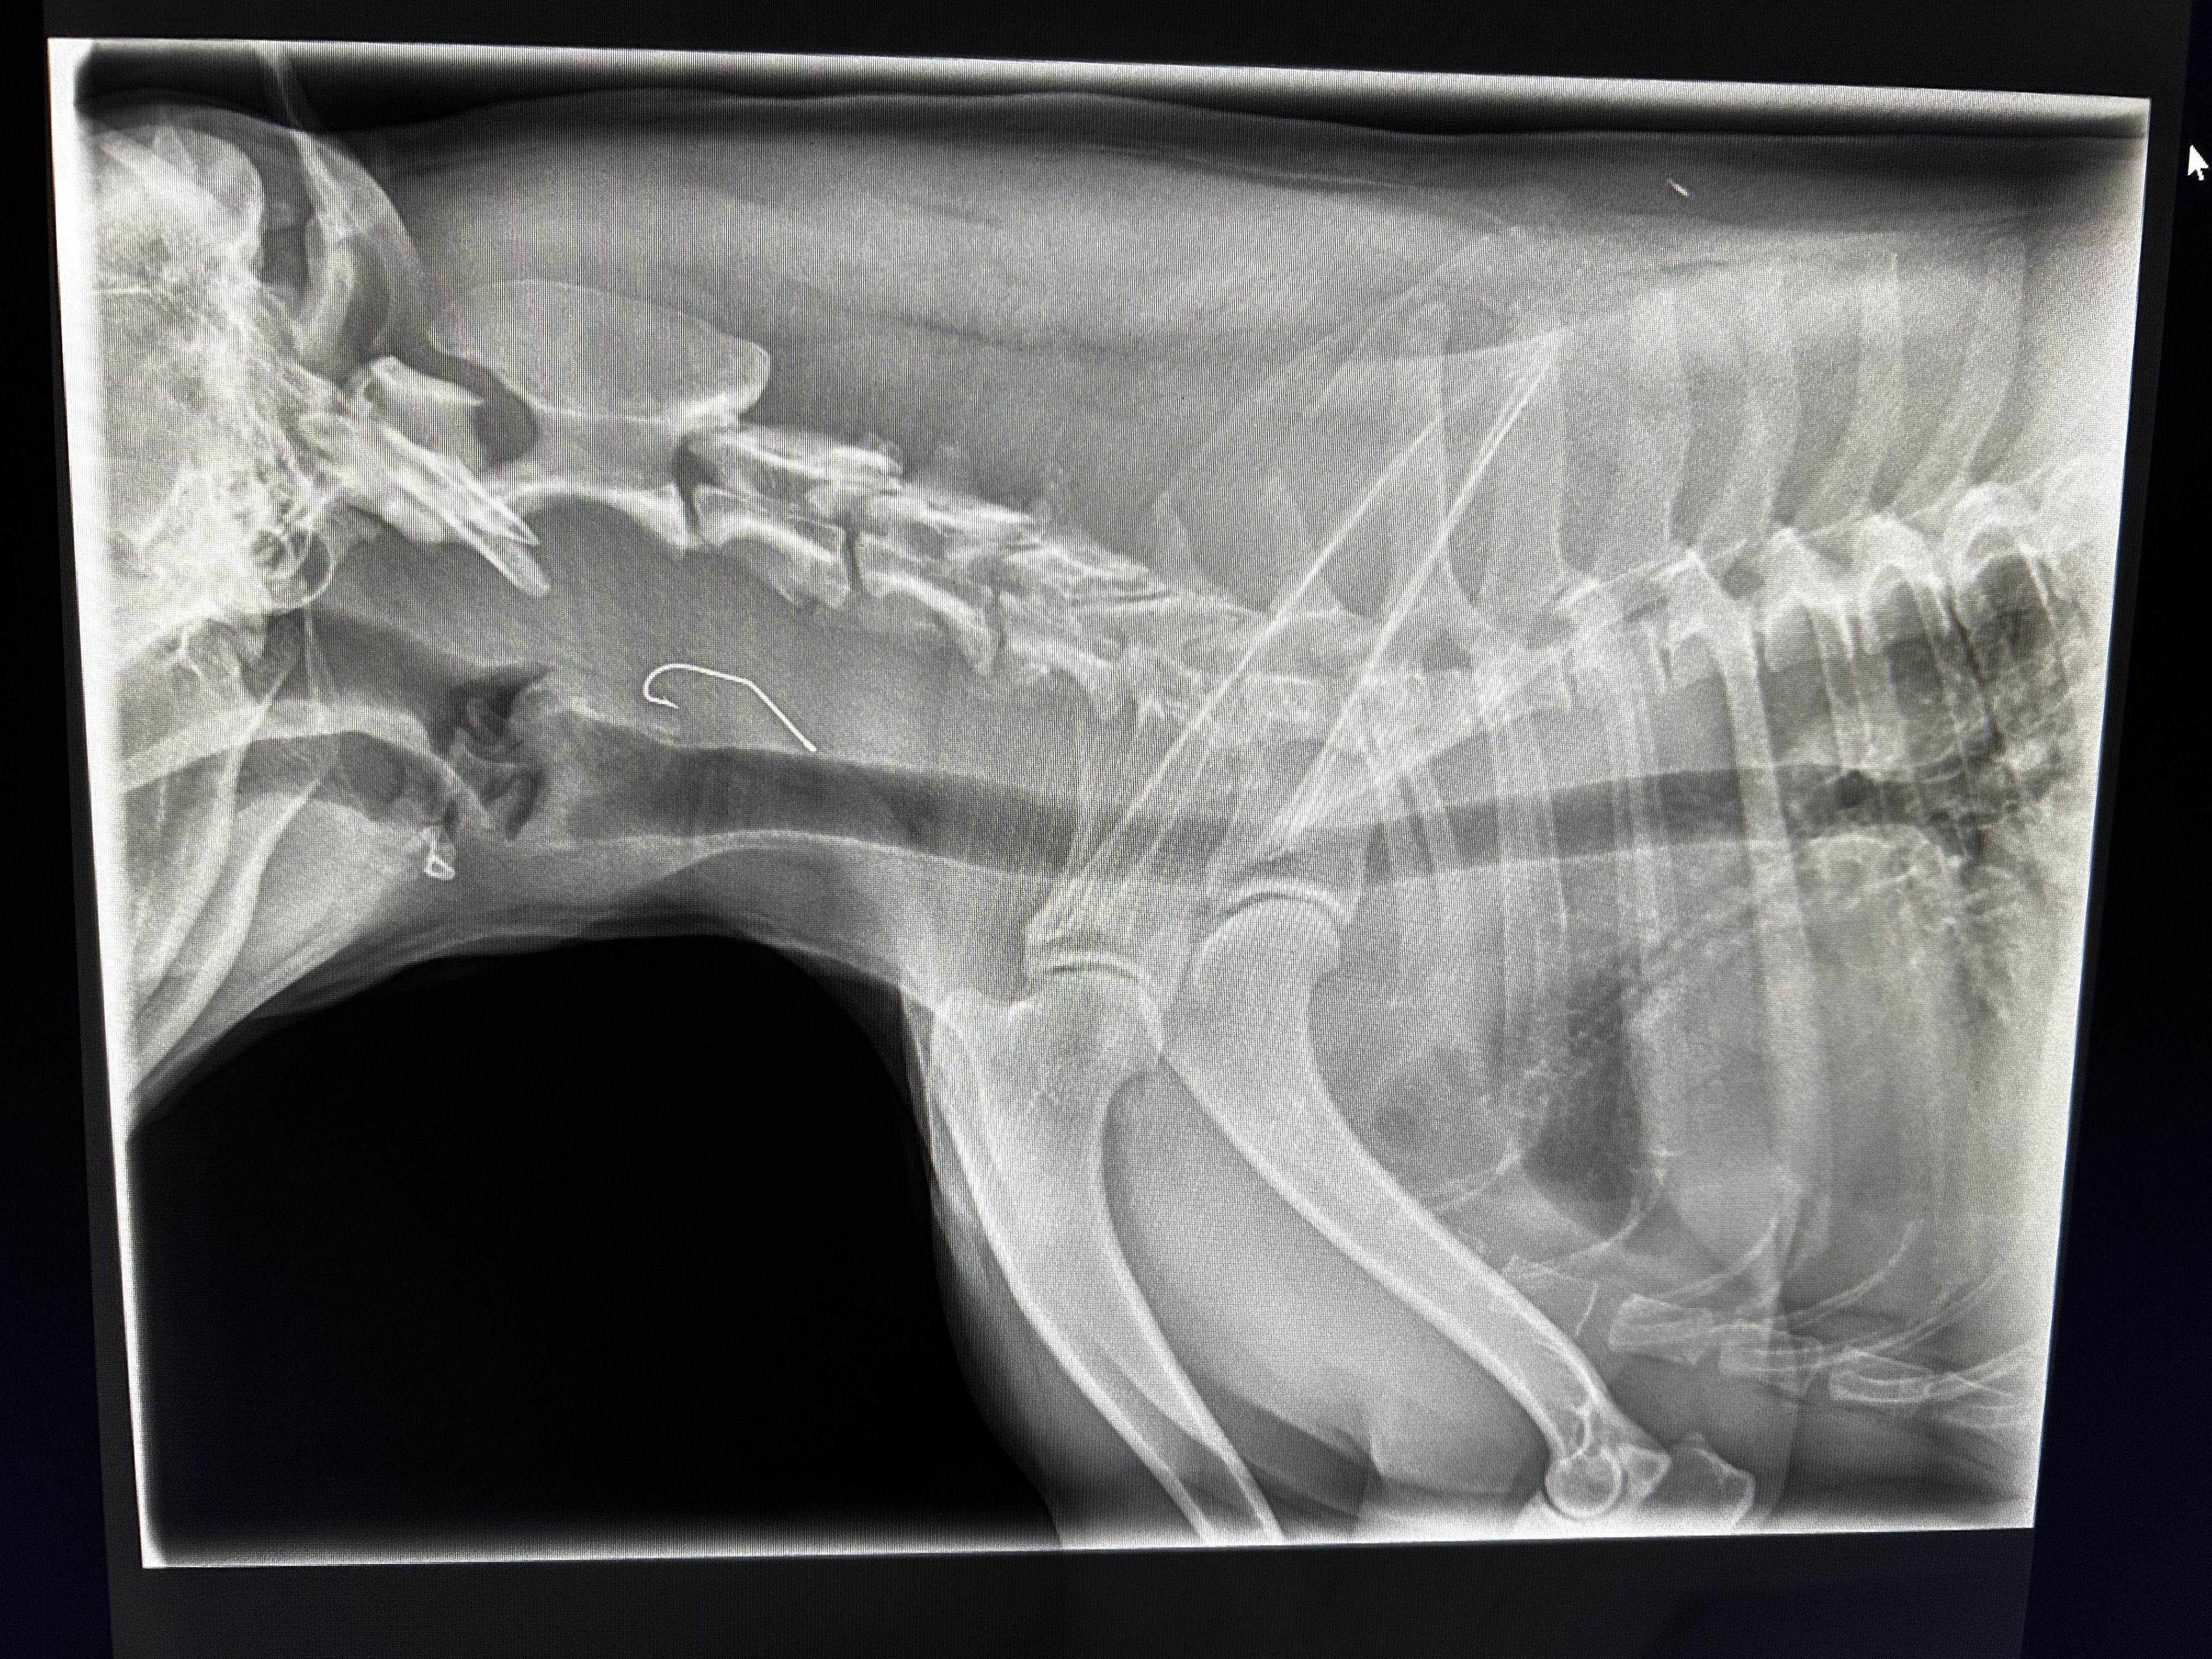

From blood testing and cytology to ultrasound, echocardiography and digital radiography, our facilities and expertise ensure you receive rapid, reliable answers - and your pet gets the right treatment without unnecessary delay.